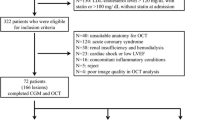

A total of 76 consecutive patients with ACS who met the inclusion and exclusion criteria and underwent both IB-IVUS and CGMS examinations were enrolled in this study. Nineteen were excluded because of poor-quality IVUS images (5 patients), stent thrombosis (1 patient), no IVUS imaging before PCI (5 patients), or insufficient CGMS data for analysis (8 patients). As a result, 57 data from 57 patients were analyzed. As seen in Table 1, the average age was 65 ± 12 years, and the majority of patients were men. The proportion of STEMI was 77.2 % and DM was 49.1 %. HbA1c and FPG values were 6.1 ± 1.0 % and 109 ± 17 mg/dl, respectively. HOMA-IR values (insulin resistance) were 2.1 ± 1.4. The percentage of patients treated with statins before admission was 21.1 % and LDL-C values at admission were 128 ± 36 mg/dl.